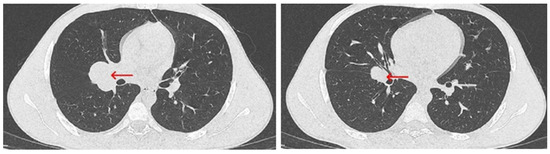

2. Case Report